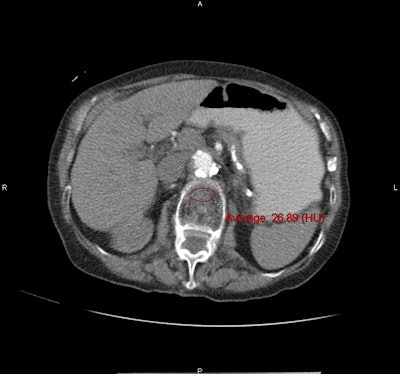

Along with the conventional DEXA exams, CT bone mineral density was measured by choosing a region of interest over vertebral trabecular bone, and measuring Hounsfield units, being careful not to exclude areas that might distort the reading.

Thus, DEXA results applied across the range of CT attenuation results were used to set thresholds that would yield either the 90% sensitivity or 90% sensitivity outcome, or a balance between the two when needed to distinguish osteoporosis from osteopenia. Specifically, an attenuation threshold of 160 HU or less was 90% sensitive, and a threshold of 110 HU was more than 90% specific for distinguishing osteoporosis from osteopenia and normal bone mineral density, the group reported.

CT attenuation values were significantly lower at all vertebral levels for patients with osteoporosis at DEXA (p < 0.001) at the L1 level. Positive predictive values for osteoporosis were 68% or greater at CT attenuation thresholds less than 100 HU; negative predictive values were 99% at thresholds greater than 200 HU, the group reported.

"You can't really talk in terms of accuracy, because it's very hard to compare the DEXA [to CT], but it's pretty clear that when somebody has a 100 HU or lower in the spine, [the patient] is very likely to have osteoporosis, and they might even have a fracture that we can directly see," Pickhardt said. "A lot of these people have been unscreened, or even missed at DEXA, so it's something that radiologists and others need to be aware of."